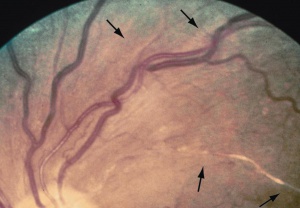

Signs

The signs of hypertensive retinopathy include constricted and tortuous arterioles, retinal hemorrhage (Figure 1, 2, and 3), hard exudates (Figure 2), cotton-wool spots (Figure 1 and 3), retinal edema, and papilledema (Figure 3). The signs of chronic arterial hypertension in the retina include widening of the arteriole reflex, arteriovenous crossing signs, and copper (Figures 1 and 3) or silver wire arterioles (copper- or silver-colored arteriole light reflex).[4]

- Grade 2: Obvious arterial narrowing with focal irregularities (Figure 1)

- Stage 2: Stage 1 + Arteriovenous crossing sign (Figure 3)

- Stage 3: Copper wiring of arterioles (copper-colored arteriole light reflex)

- Stage 4: Silver wiring of arterioles (silver-colored arteriole light reflex).